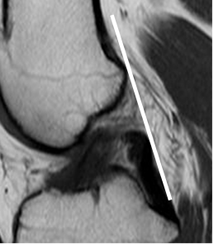

Fig 101. Ruptura del LCA.

A y B: RM sagital en T2. Signos de ruptura, con disminución del ángulo de inclinación tibial en A y ángulo con la línea intercondílea, de vértice inferior en B.